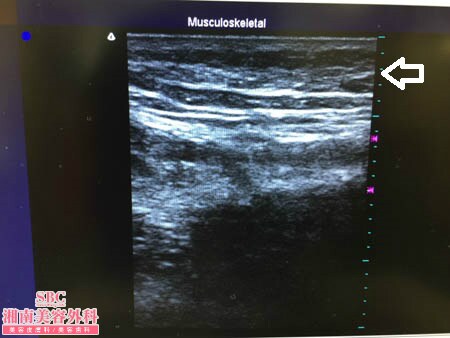

No.176472【脂肪吸引】芸能人の患者様!太ももの脂肪吸引に満足して次はふくらはぎを細くする!術中3Dタッチビュー・左ふくらはぎ

いつものように3Dタッチビュー(超音波)で

皮下脂肪層を評価してみましょう。